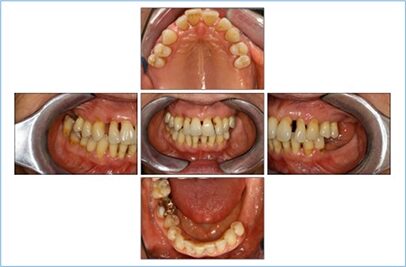

DermanNach Extraktion der nichterhaltungswürdigen Zähne und antiinfektiöser Therapie mit subgingivaler Instrumentierung nach Stufe 2 konnte zur ersten Reevaluation eine nahezu komplette „pocket-closure“ erreicht werden. Daraufhin erfolgte in Stufe 3 lokalisiert eine subgingivale Reinstrumentierung und – nachdem durch vorangegangene Einschleifmaßnahmen die Zähne 12 und 22 in Zentrik und Laterotrusion nicht mehr ausgelenkt wurden – auch eine SÄT-Schienung (13/12 und 21/22) mit Contouring zur ästhetischen Maskierung der durch Auffächerung entstandenen Lücken (Abb. 6). In Stufe 4 – der unterstützenden Parodontitistherapie – konnte die risikobasierte Frequenz von 3 Monaten (Grad C) durch die Patientin nicht eingehalten werden und es kam in den hier berichteten 9 Jahren UPT lediglich zu 16 UPT-Sitzungen. Somit wurden weniger als 50% der empfohlenen UPT-Sitzungen wahrgenommen. Dennoch zeigten sich die parodontalen Parameter weitgehend stabil (Abb. 7). Aufgrund eines generalisierten Rezidivs wurde im Rahmen der 13. UPT-Sitzung nochmals eine subgingivale Instrumentierung durchgeführt. Dieses Rezidiv ging mit der Erstmanifestation eines Lichen ruber planus einher, der auf den Abschlussbildern (Abb. 8) mit der charakteristischen Wickham-Streifung in den Wangeninnenseiten auch noch zu erkennen ist, wobei wieder ein stabiler parodontaler Zustand erreicht werden konnte (Abb. 9).

DermanAuch wenn die stark parodontal kompromittierte Situation nun schon seit rund 16 Jahren durch eine überdurchschnittliche Mitarbeit der Patientin hinsichtlich der Mundhygiene erhalten werden konnte, ist dies trotzdem nicht als langzeitstabil zu werten. Dennoch hat sich die Prognose im Vergleich zur Anfangssituation deutlich verbessert (Tab. 5). Entsprechend der Klassifikation (EFP/AAP 2018) lautet die Abschlussdiagnose wie folgt: